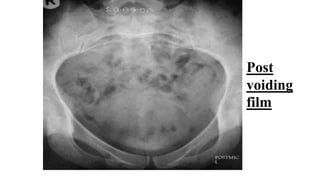

•Post voiding film :

•-Residual urine

•-Contrast left on upper tract? (normally there is

no contrast left on upper urinary tract on post

voiding film)

Post

voiding

film